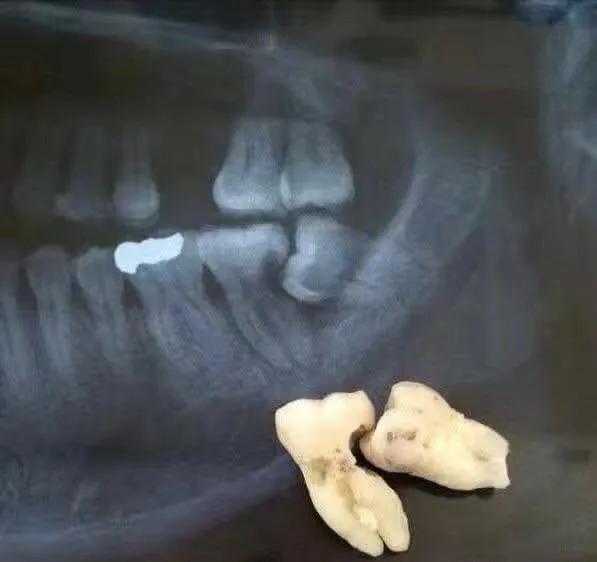

您下面智齒斜著長的,跟前面的第二磨牙經(jīng)常性食物嵌塞,把第二磨牙的鄰面蛀壞了,拍個片子看看吧。

您兩邊的智齒都把前面的第二磨牙頂壞了,治療計劃是拔除智齒,治療第二磨牙,要來好幾次了,費用也不低。

鄰牙損壞:

智齒生長可能對鄰牙造成擠壓,導致鄰牙損壞或移位。智齒與鄰牙之間容易嵌塞食物,難以清潔,長期下來可能導致鄰牙齲壞。

智齒齲壞:當智齒出現(xiàn)嚴重齲壞,且治療價值不大時,建議拔除,這包括鄰接面齲壞難以處理或需要根管治療的情況。

影響其他牙齒:智齒的生長可能對鄰牙造成擠壓,導致鄰牙損壞或移位。在這種情況下,為了保護其他牙齒的健康,需要拔除智齒。

嚴重食物嵌塞:智齒位置不良,容易與前牙食物嵌塞,建議拔除。